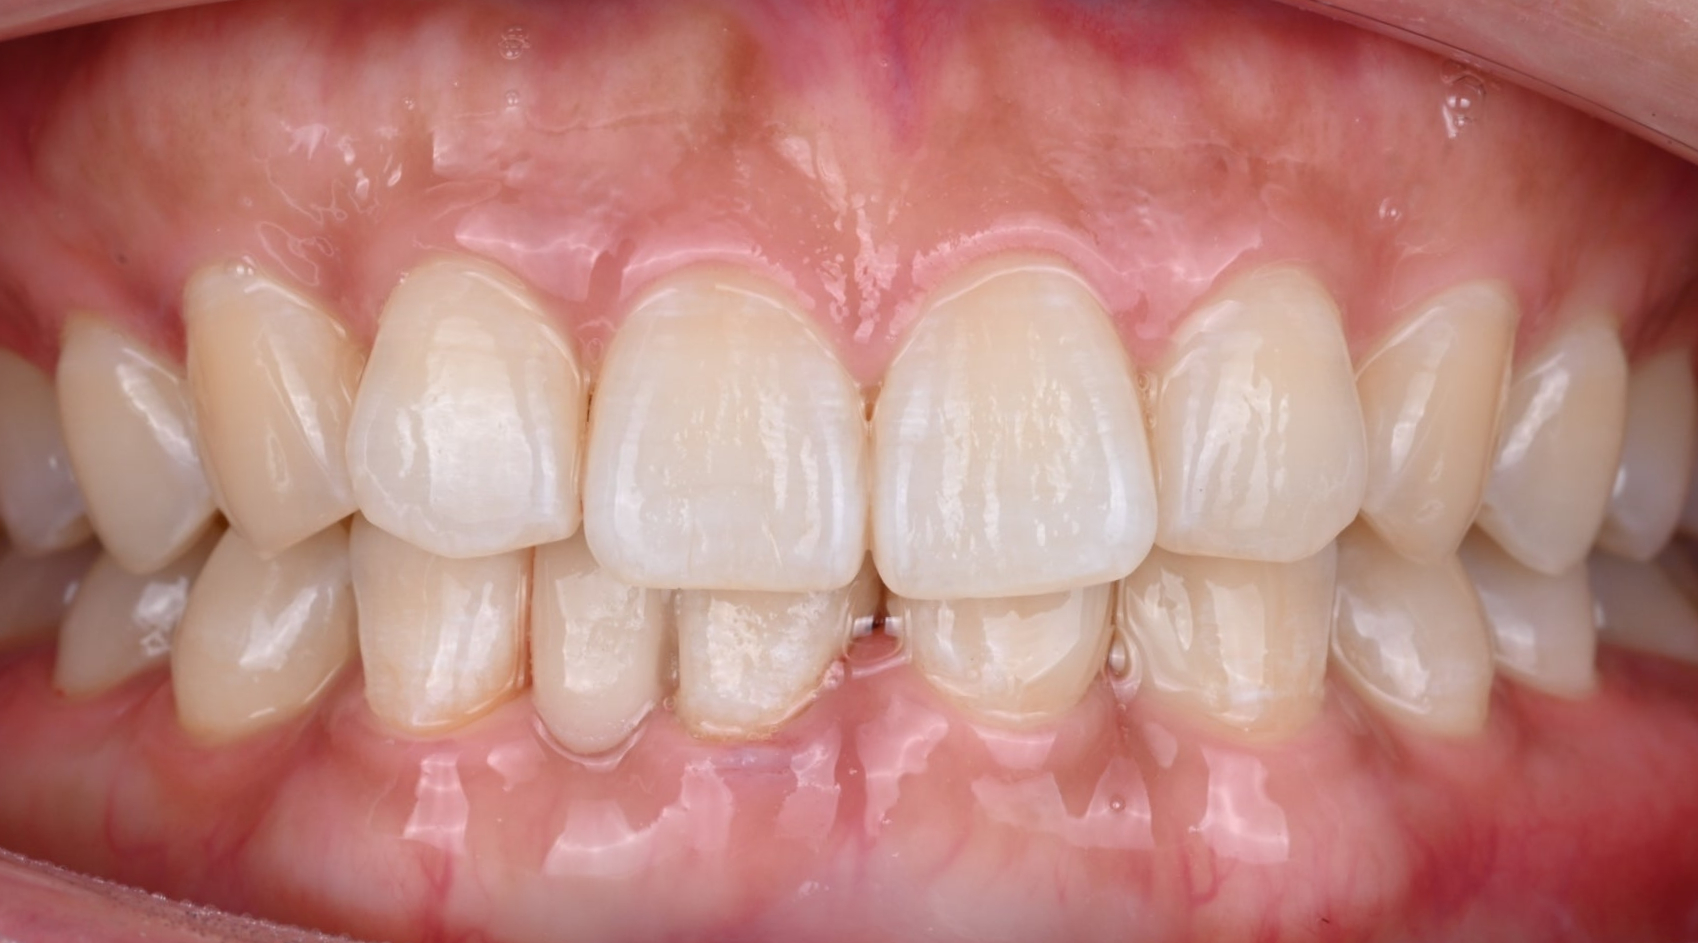

26.04.02 메릴랜드 브릿지 접착 후

26.04.02 치료 후 모습

26.04.02 치료 후